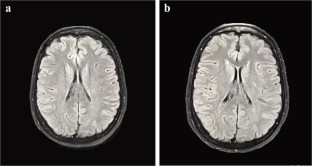

Silent brain lesions might be associated with overt cerebrovascular accident over time in beta thalassemia major (BTM) and intermediate (BTI). Aspirin may be protective in these patients. We evaluated brain magnetic resonance imaging (MRI) in thalassemia patients to see whether aspirin is protective or not. A historical cohort study was conducted on 35 thalassemia patients, 22 BTI, and 13 BTM patients at Shiraz Hematology Research Center in 2018. Median age of the patients was 32 years and ranged from 8 to 42 years. Twenty-four patients (68.6%) were females. Overall frequency of white matter lesions (WMLs) in the first MRI was 10 patients (28.6%). After 3 years, 3 patients developed new lesions and the frequency of WMLs was 13 patients (37.1%) in the second MRI. Moreover, in 3 patients, number of WMLs increased. Patients with new lesions or more lesions compared to the baseline were significantly older than the other group (median age 36.5 years vs. 31 years, P = 0.046). Regarding aspirin consumption, only 1 patient (16.7%) of patients with new lesions was using aspirin compared to 10 (34.5%) of the other group (P = 0.640). The high-risk patients with thrombocytosis, splenectomy, severe iron overload, and older age (> 30 years) should be under close follow-up and evaluated on a regular periodic basis as well as brain MRI at least once every 3 years. Aspirin could be protective against new or progressive brain lesions so that low-dose aspirin is recommended in high-risk thalassemia patients.